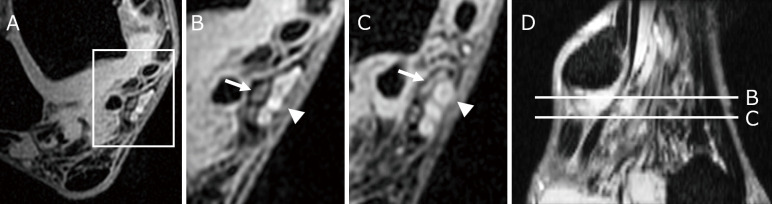

跗骨隧道综合征是一种位于跗骨隧道的压迫性神经病变。诊断和预测手术结果是困难的。我们比较了术前和术后的磁共振成像结果。我们检查了连续38例跗骨隧道综合征(47英尺)患者的术前磁共振成像结果;他们的平均年龄为73.8岁。我们在术前T2*脂肪抑制轴向磁共振成像图像上观察最受压神经切片上的神经宽度和该神经的高强度,并探讨磁共振成像在跗骨隧道综合征患者的诊断和手术结果中的作用。术后症状明显改善。术前磁共振成像扫描显示,最受压神经的平均宽度为0.99±0.37 mm。术前症状严重程度与术后症状改善无显著相关性。在29英尺(61.7%),我们观察到压迫神经的高强度。除一只脚外,其余足部均在靠近最强神经压迫点的3个轴向切片上显示高信号区。术前有高强度(1组,n = 29)和无高强度(2组,n = 18)患者的症状严重程度无显著差异。组1患者最大受压点神经宽度明显变细,术后症状改善明显较大。虽然术前神经压迫严重程度与手术结果之间没有相关性,但磁共振成像扫描显示的神经高强度可能有助于跗骨隧道综合征的诊断。

Tarsal tunnel syndrome is an entrapment neuropathy at the tarsal tunnel. The diagnosis and the prediction of the surgical outcome are difficult. We compared preoperative magnetic resonance imaging findings with the postoperative results. We examined preoperative magnetic resonance imaging findings in 38 consecutive patients with Tarsal tunnel syndrome (47 feet); their mean age was 73.8 years. We inspected the nerve width on the slice showing the most compressed nerve, and the hyperintensity of that nerve on preoperative T2* fat-suppressed axial magnetic resonance imaging images and examined the role of magnetic resonance imaging in the diagnosis and of the surgical outcomes in patients with Tarsal tunnel syndrome. Postoperatively, there was significant symptom improvement. On preoperative magnetic resonance imaging scans the mean width of the most compressed nerve was 0.99 ± 0.37 mm. There was no significant correlation between the preoperative symptom severity and postoperative symptom improvement. In 29 feet (61.7%) we observed hyperintensity of the compressed nerve. In all but one foot the hyperintense area was displayed on 3 axial slices adjacent to the strongest nerve compression point. There was no significant difference in the preoperative symptom severity in patients with (group 1, n = 29) or without hyperintensity (group 2, n = 18). The nerve width at the point of greatest compression was significantly thinner, and postoperative symptom improvement was significantly greater in group 1 patients. Although there was no correlation between the preoperative nerve compression severity and the surgical results, nerve hyperintensity on magnetic resonance imaging scans may help with the diagnosis of Tarsal tunnel syndrome.